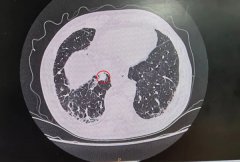

【精准“导航”+无痛定位】南通六院胸外科黑科技让“刁钻”肺结节无处可藏!

肺结节位置太深、藏在骨头缝里? 传统定位又疼又有辐射? 别担心!南通六院胸外科黑科技 CT三维数据融合式经皮穿刺导航定位术 2分钟精准锁定病灶,...